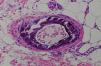

Una biopsia cutánea de la zona afecta demostró ulceración superficial con necrosis del colágeno de la dermis superficial; así como una calcificación extensa y proliferación de la íntima de la pared de múltiples arterias y arteriolas (fig. 2). Los depósitos de calcio en la pared vascular fueron más evidentes con la tinción de Von Kossa. No se observó depósito de calcio extravascular ni necrosis grasa, confirmándose el diagnóstico de calcifilaxia. Debido a que no existía deficiencia de proteína C o S, ni alteraciones en los niveles de hormona paratiroidea, calcio y fosfato sérico, se estableció el diagnóstico de calcifilaxia atípica.